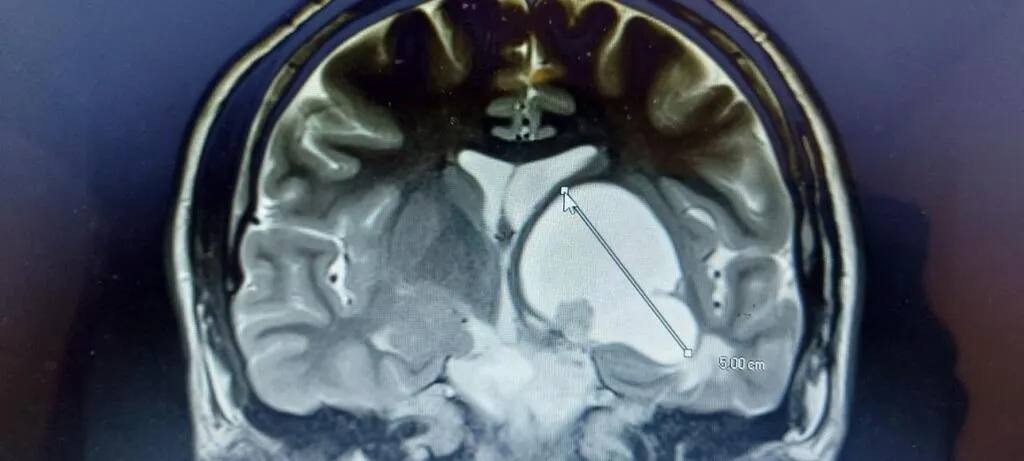

En 2008, Philippe et Fabienne Léon découvraient la présence d’une tumeur de quatre centimètres dans le cerveau de leur fils Nathanaël, alors âgé de 5 ans. Deux ans plus tard, ils créaient l’association Un geste, un rêve un sourire. Depuis, ils se démènent pour améliorer le quotidien des enfants malades et handicapés.